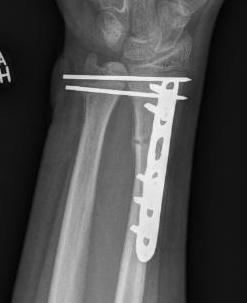

Operative management

1. Anatomical ORIF of distal radius with dynamic compression plate

- anatomical reduction

- restoration of radial bow

- compression for healing

Radius ORIF with dynamic compression plates